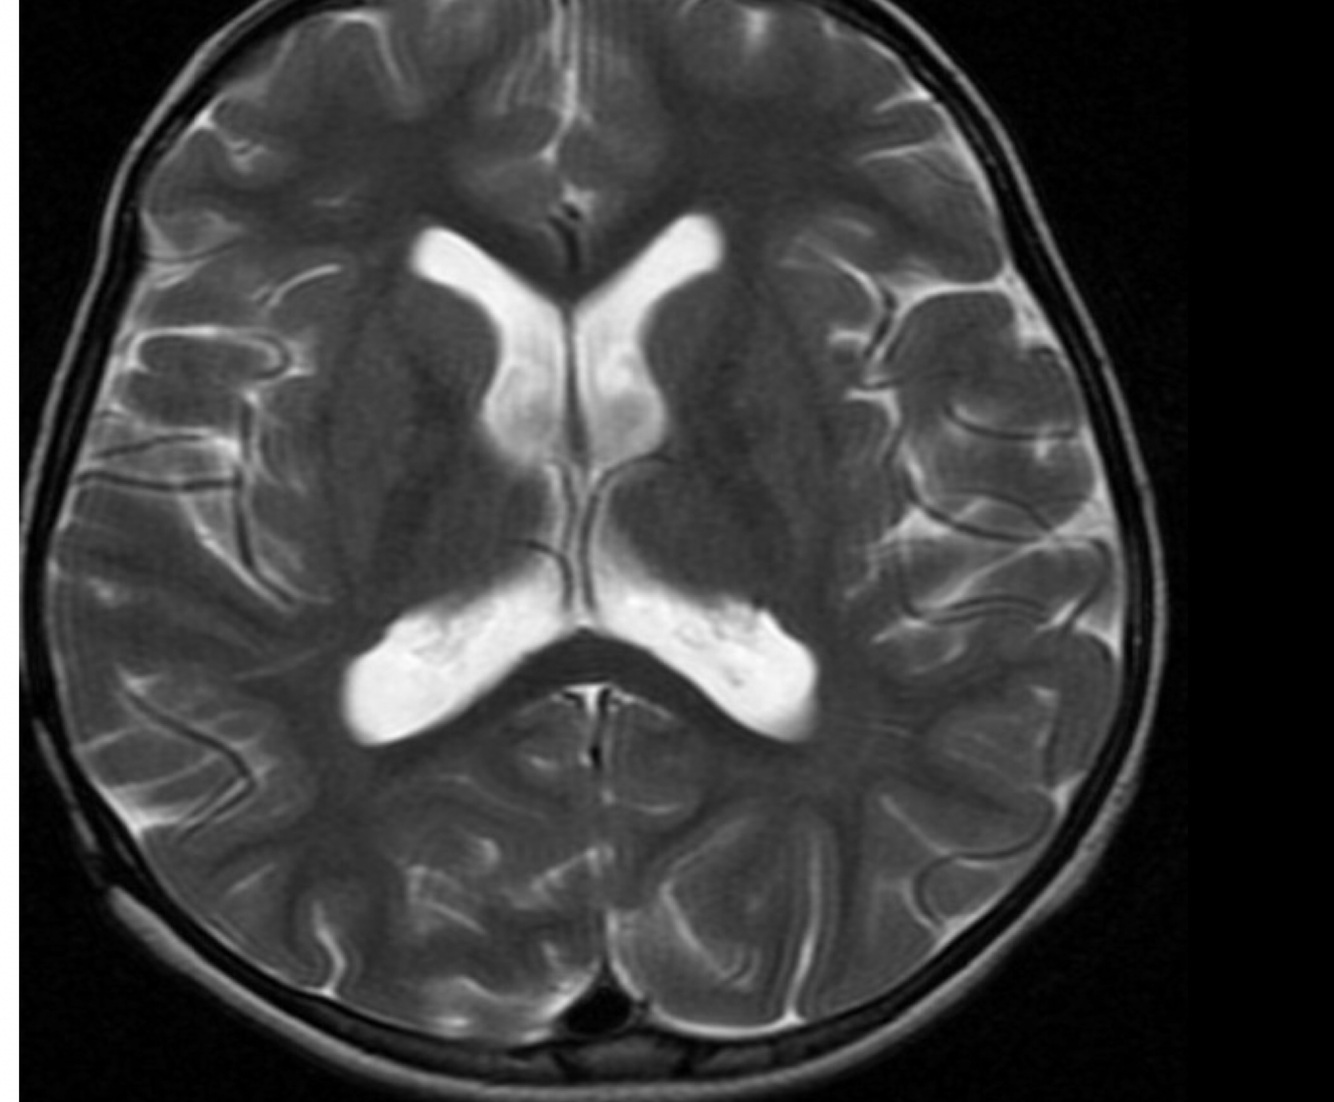

Aliasing on MRI, also known as wrap-around, is a frequently encountered MRI artifact that occurs when the field of view (FOV) is smaller than the body part being imaged. The part of the body that lies beyond the edge of the FOV is projected onto the other side of the image. This can be corrected, if necessary, by oversampling the data. In the frequency direction, this is accomplished by sampling the signal twice as fast. In the phase direction, the number of phase-encoding steps must be increased with a longer study as a result. However, if the FOV and matrix size (phase-encoding steps) are increased and simultaneously number of excitations (or number of signal averages) reduced to half, the imaging time can be kept constant with correction of aliasing. Case 1 demonstrates axial T2-weighted images of the brain that demonstrates aliasing. The first image shows wrap-around with the back of the head projected over the front because the phase-encoded direction is anterior-posterior and the FOV is too small.

Fix: phase and frequency directions reversal resulting in absence of the aliasing artifact. Oversampling is used in the phase direction to eliminate the aliasing.